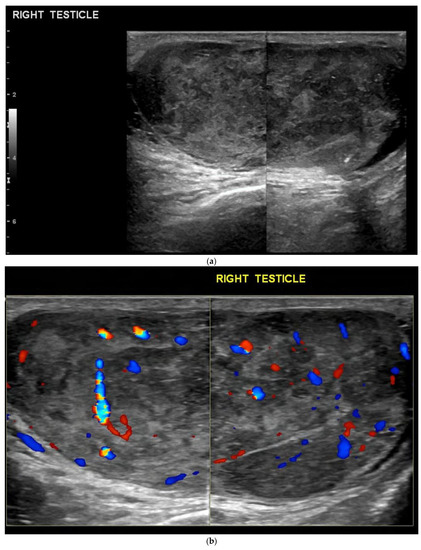

4.2. Non-Seminomatous Germ Cell Tumour (NSGCTs)

4.3. Embryonal Cell Carcinoma

| Non-seminomas | Heterogenous Irregular margins Cystic and calcification components seen commonly |

| Pure embryonal | Heterogeneously hypoechoic Ill-defined margins with invasion of the tunica albuginea Can contain haemorrhage and calcifications |